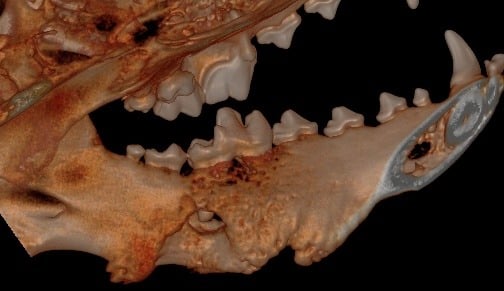

Below: 3D Hard Tissue Overview (left side)

.jpg?width=790&height=486&name=3D%20Hard%20Tissue%20Overview%20(left%20side).jpg)